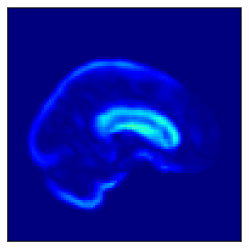

Fig. 5 shows the difference in the reconstructed images (the coronal, sagittal, transverse planes) with and without perturbation to one dimension of the low-dimensional representations that most affect the disease features between AD and CN. This one dimension is chosen to have the largest expected value of the difference in the mean vector ( dim) between AD and CN.

In Fig. 5, the influence of dimensions that may contribute to the diagnosis of AD is examined, and it can be seen that the naïve -VAE captures not only the important areas around the ventricles shown in Fig. 2 but also the edges of the brain and other areas. Loc-VAE, however, is more limited and captures this region better. This result shows that Loc-VAE acquires a specific dimension of the disease features on low-dimensional representation. Disease feature–specific dimensions serve as materials for the neurologist to assess similar cases displayed by CBIR.